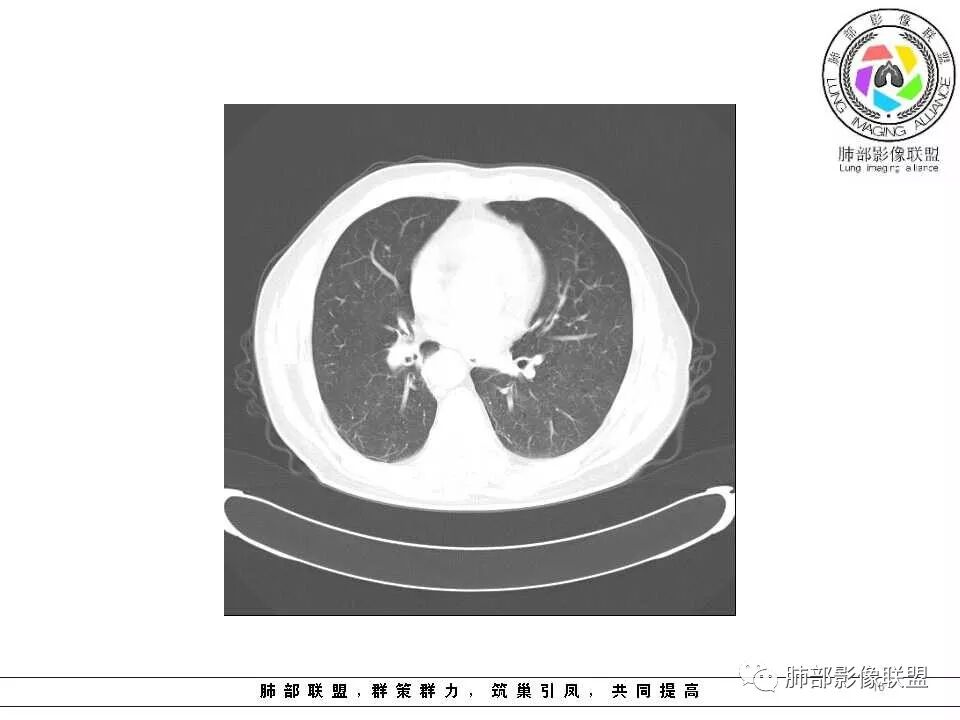

影像学特点:肺气肿背景下在大概一年的时间里出现了一个光滑的小结节,因为图像给的不是太薄,与支气管的关系判断不清,从结节周围出现斑片状炎症来判断,应该考虑结节位于支气管内,周围是阻塞性炎症,这样比较容易解释咯血

纵隔窗上似乎结节内可见点状高密度影,同时没有明显肿大淋巴结

左肺上叶光滑结节影 似乎与支气管没有关系  ,给的纵隔窗病灶中心似乎点状钙化  病灶旁有更小结节,与上一年片比较 结节增大明显  考虑恶性 类癌可能

老年男性,两肺可见小叶中央型肺气肿,提示应该有抽烟史。2016年片,右肺门支气管稍模糊,考虑慢性感染,纵膈淋巴结稍大。但2017年左肺上叶新发占位,堵塞支气管,引起局部肺不张伴感染,且纵膈淋巴结较2016年变大,患者同时伴有咯血,考虑恶性。鳞癌?类癌?小细胞?

肺气肿背景,2016年左肺上叶上舌段见微结节,2017年5月左肺结节增大,密度均匀,边缘光滑锐利,与邻近血管关系密切,血管贴壁走行,外侧见尖状突起,下舌段片状影,沿着支气管走行,内有粘液栓,考虑鳞癌,鉴别小细胞肺癌。

肺气肿背景,2016年左肺上叶上舌段见微结节,一年后左肺结节增大,密度均匀,边缘光滑、膨隆,似见小分叶,下舌段片状影,沿着支气管走行,内,老年患者,咯血1月。考虑恶性病变并阻塞性肺炎,鳞癌?注意鉴别结核。

前次片2016年4月20相应位置就有小点状病灶,2017-5-15呈结节影改变,边界膨隆,远端阻塞炎性改变,考虑肺癌,鉴别炎性结节!